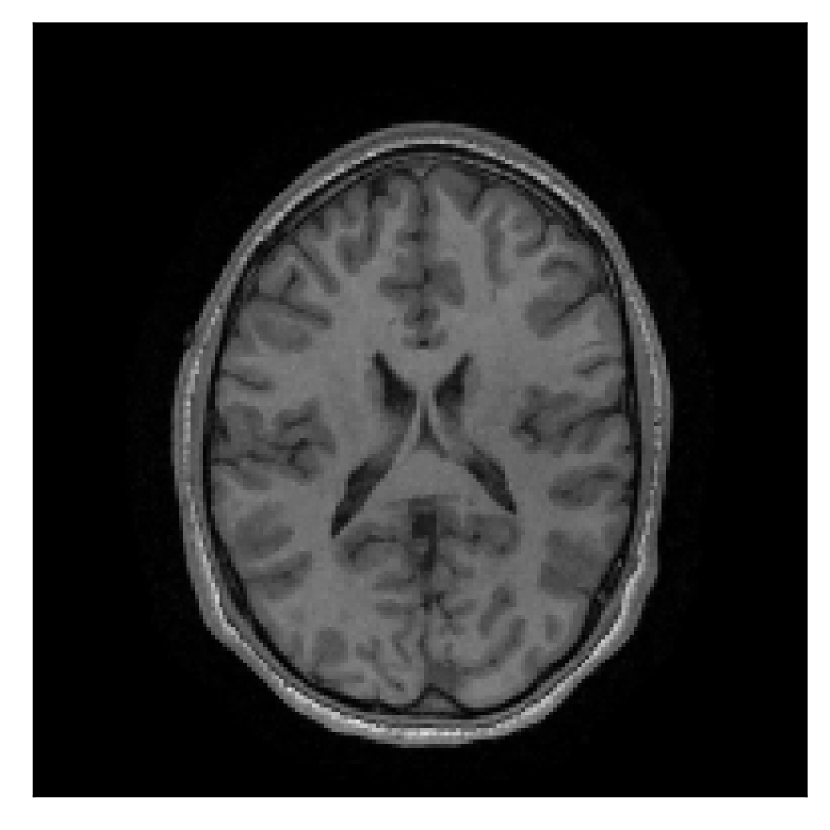

We consider three levels of motion corruption: (i) the volunteer moves once, (ii) the volunteer moves twice, and (iii) the volunteer moves five times. The volunteer is instructed to change its head position every time it is prompted to do so, and maintain that position in between instructions. We use T2-FLAIR-weighted contrasts as corrupted scans, with T1-weighted contrast as a reference (see Table 1 for further details). The corrupted acquisition employs randomized sampling.

4.1 Experiment 1: robustness test

We gather the results for the robustness test described in Section 3.1 (volunteer 1) in Figures 2, 4, and 6 for motion corruption mechanisms associated to one, two, and five changes of position, respectively. Furthermore, we juxtapose the corrected images with varying degrees of corruption in Figure 8. We observe that the proposed method consistently ameliorates the corrupted scan. The quality indexes based on PSNR and SSIM show only a modest decrease in correction quality as a function of motion complexity (Figure 8).

| Section 3.1, Figure 2 | Sagittal | 23.94 | 27.95 | 0.7068 | 0.7936 |

| Coronal | 26.66 | 29.82 | 0.7653 | 0.8332 | |

| Axial | 25.40 | 30.16 | 0.7616 | 0.8490 | |

| Section 3.1, Figure 2 | T2-FLAIR | Completely corrected | Some blurring | No additional artifacts | Good grey white matter differentiation |